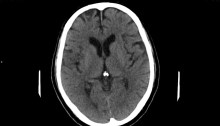

Diagnosis and Management of Transient Ischemic Attack and Acute Ischemic Stroke A Review JAMA 2021.

Esta revisión resume la evidencia actual con respecto al diagnóstico de ACV isquemico y Accidente Isquemico transitorio , métodos de manejo temprano para mejorar los resultados y prevenir accidentes cerebrovasculares isquémicos recurrentes.